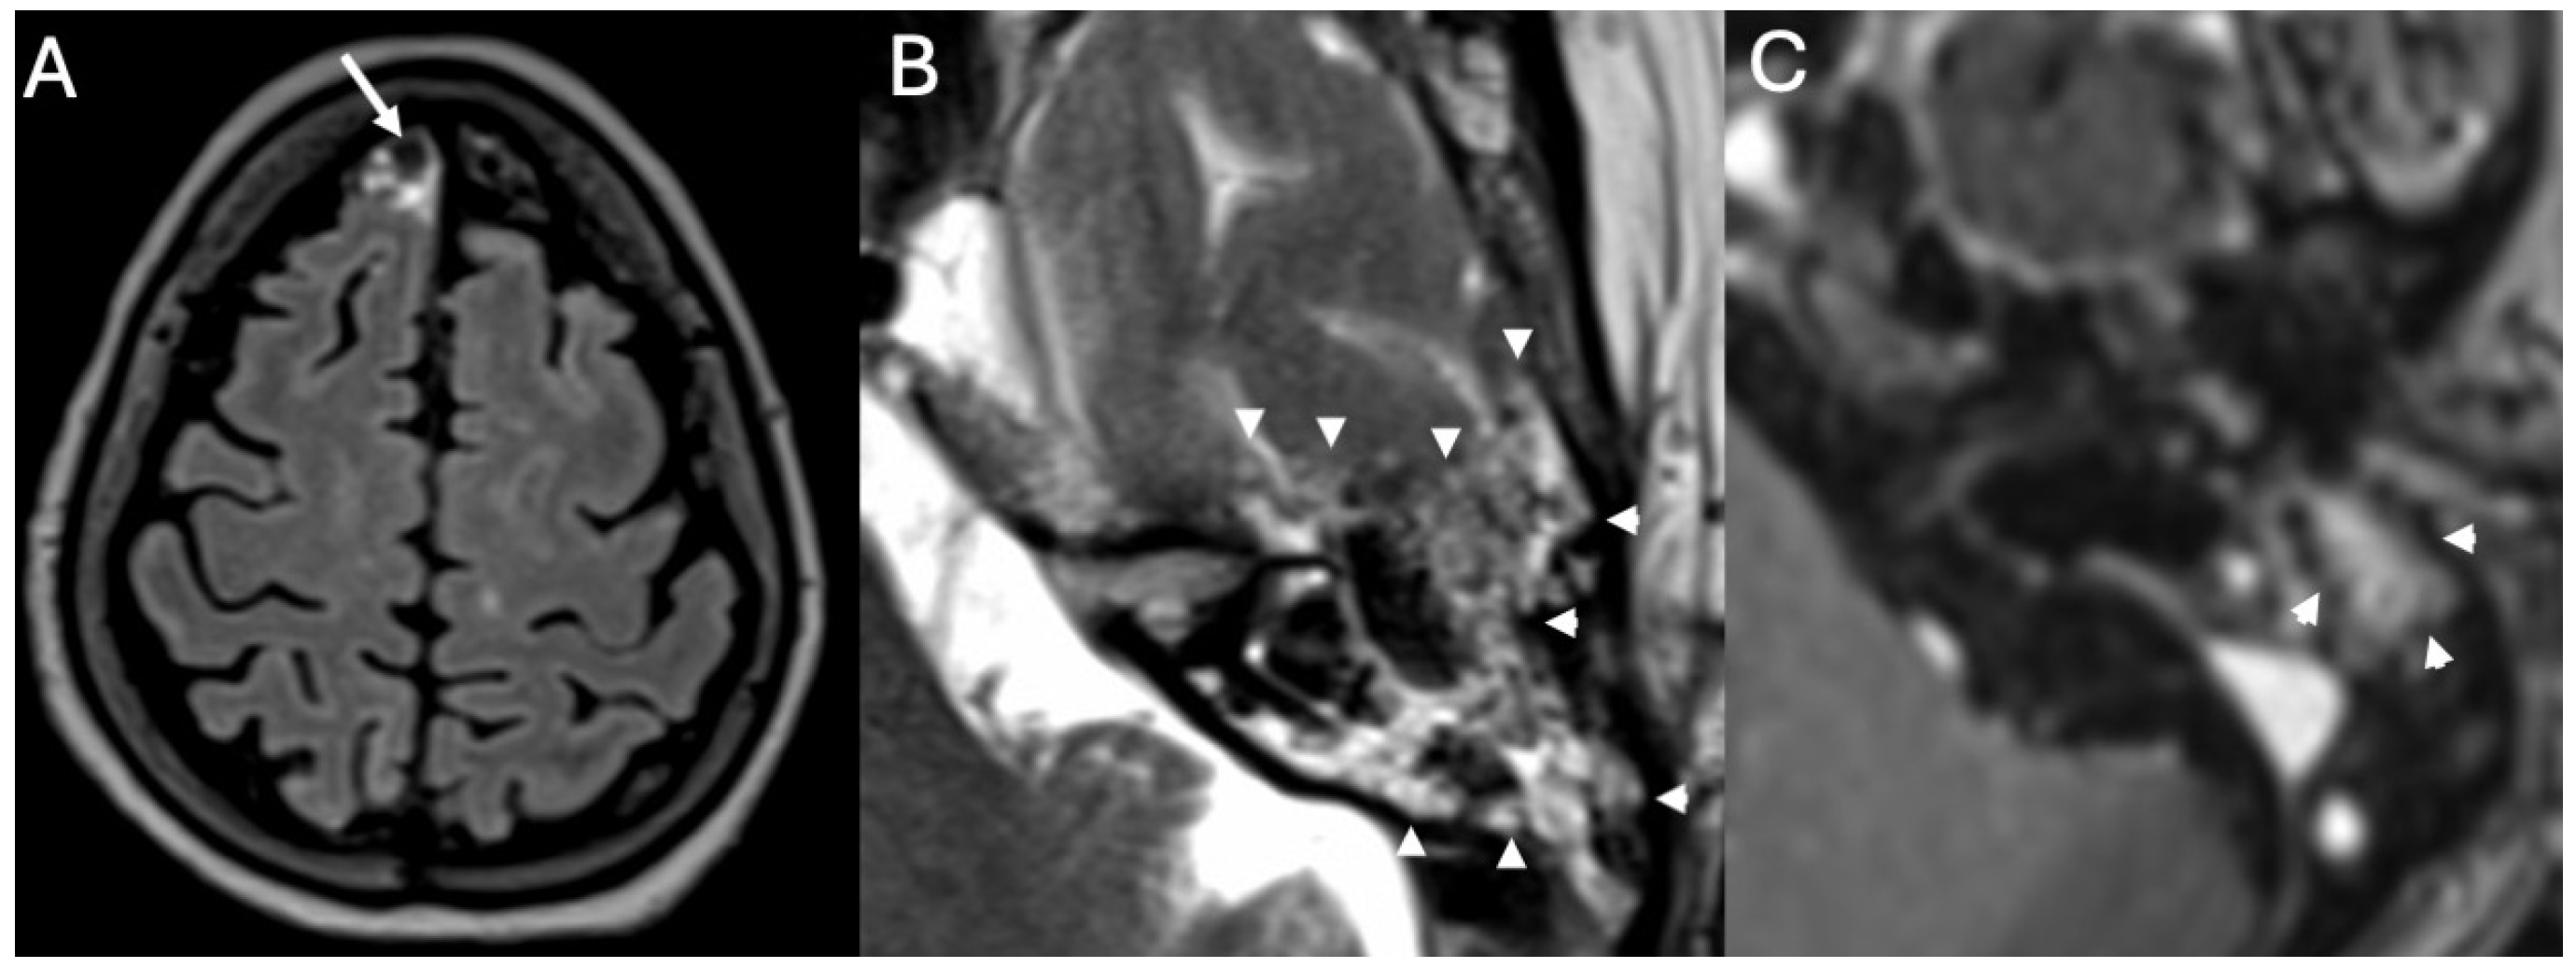

3.3.1. Imaging

3.3.2. Complications

| Cholesteatoma and Otogenic Complications | Kuo et al., 2015 [26]; Baráth et al., 2011 [27]; Mustafa et al., 2014 [28]; Dubey et al., 2010 [29]; Sun et al., 2014 [30]; Lee et al., 2020 [31] | Reviews and retrospective studies | Cholesteatoma causes erosion and CSF leak, leading to meningitis (12–30% incidence); MRI improves detection; pediatric risk emphasized. |